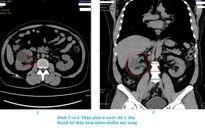

Kết quả siêu âm cho thấy âm đạo và tử cung bệnh nhi giãn lớn do máu kinh ứ đọng, tạo thành một khối chèn ép bàng quang và niệu quản. Tình trạng này khiến thận trái bắt đầu giãn, cho thấy hệ tiết niệu đã bị ảnh hưởng.